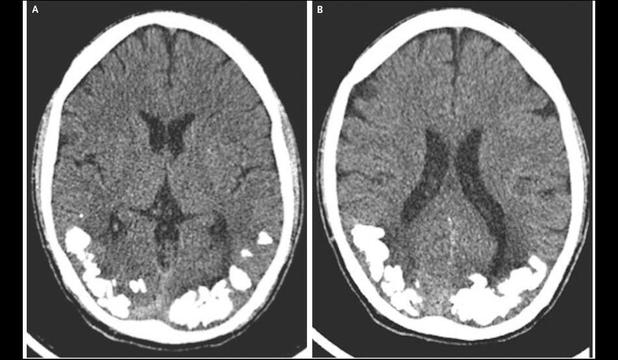

În cele din urmă, în urma unei tomografii computerizate, medicii au descoperit mai multe aglomerări solide, calcificate, în partea posterioară a creierului, în aria care procesează informaţiile vizuale. Analizele au mai arătat că în sângele pacientului exista o proporţie mare de antiocorpi asociaţi cu boala celiacă. Cazul a fost descris în New England Journal of Medicine.